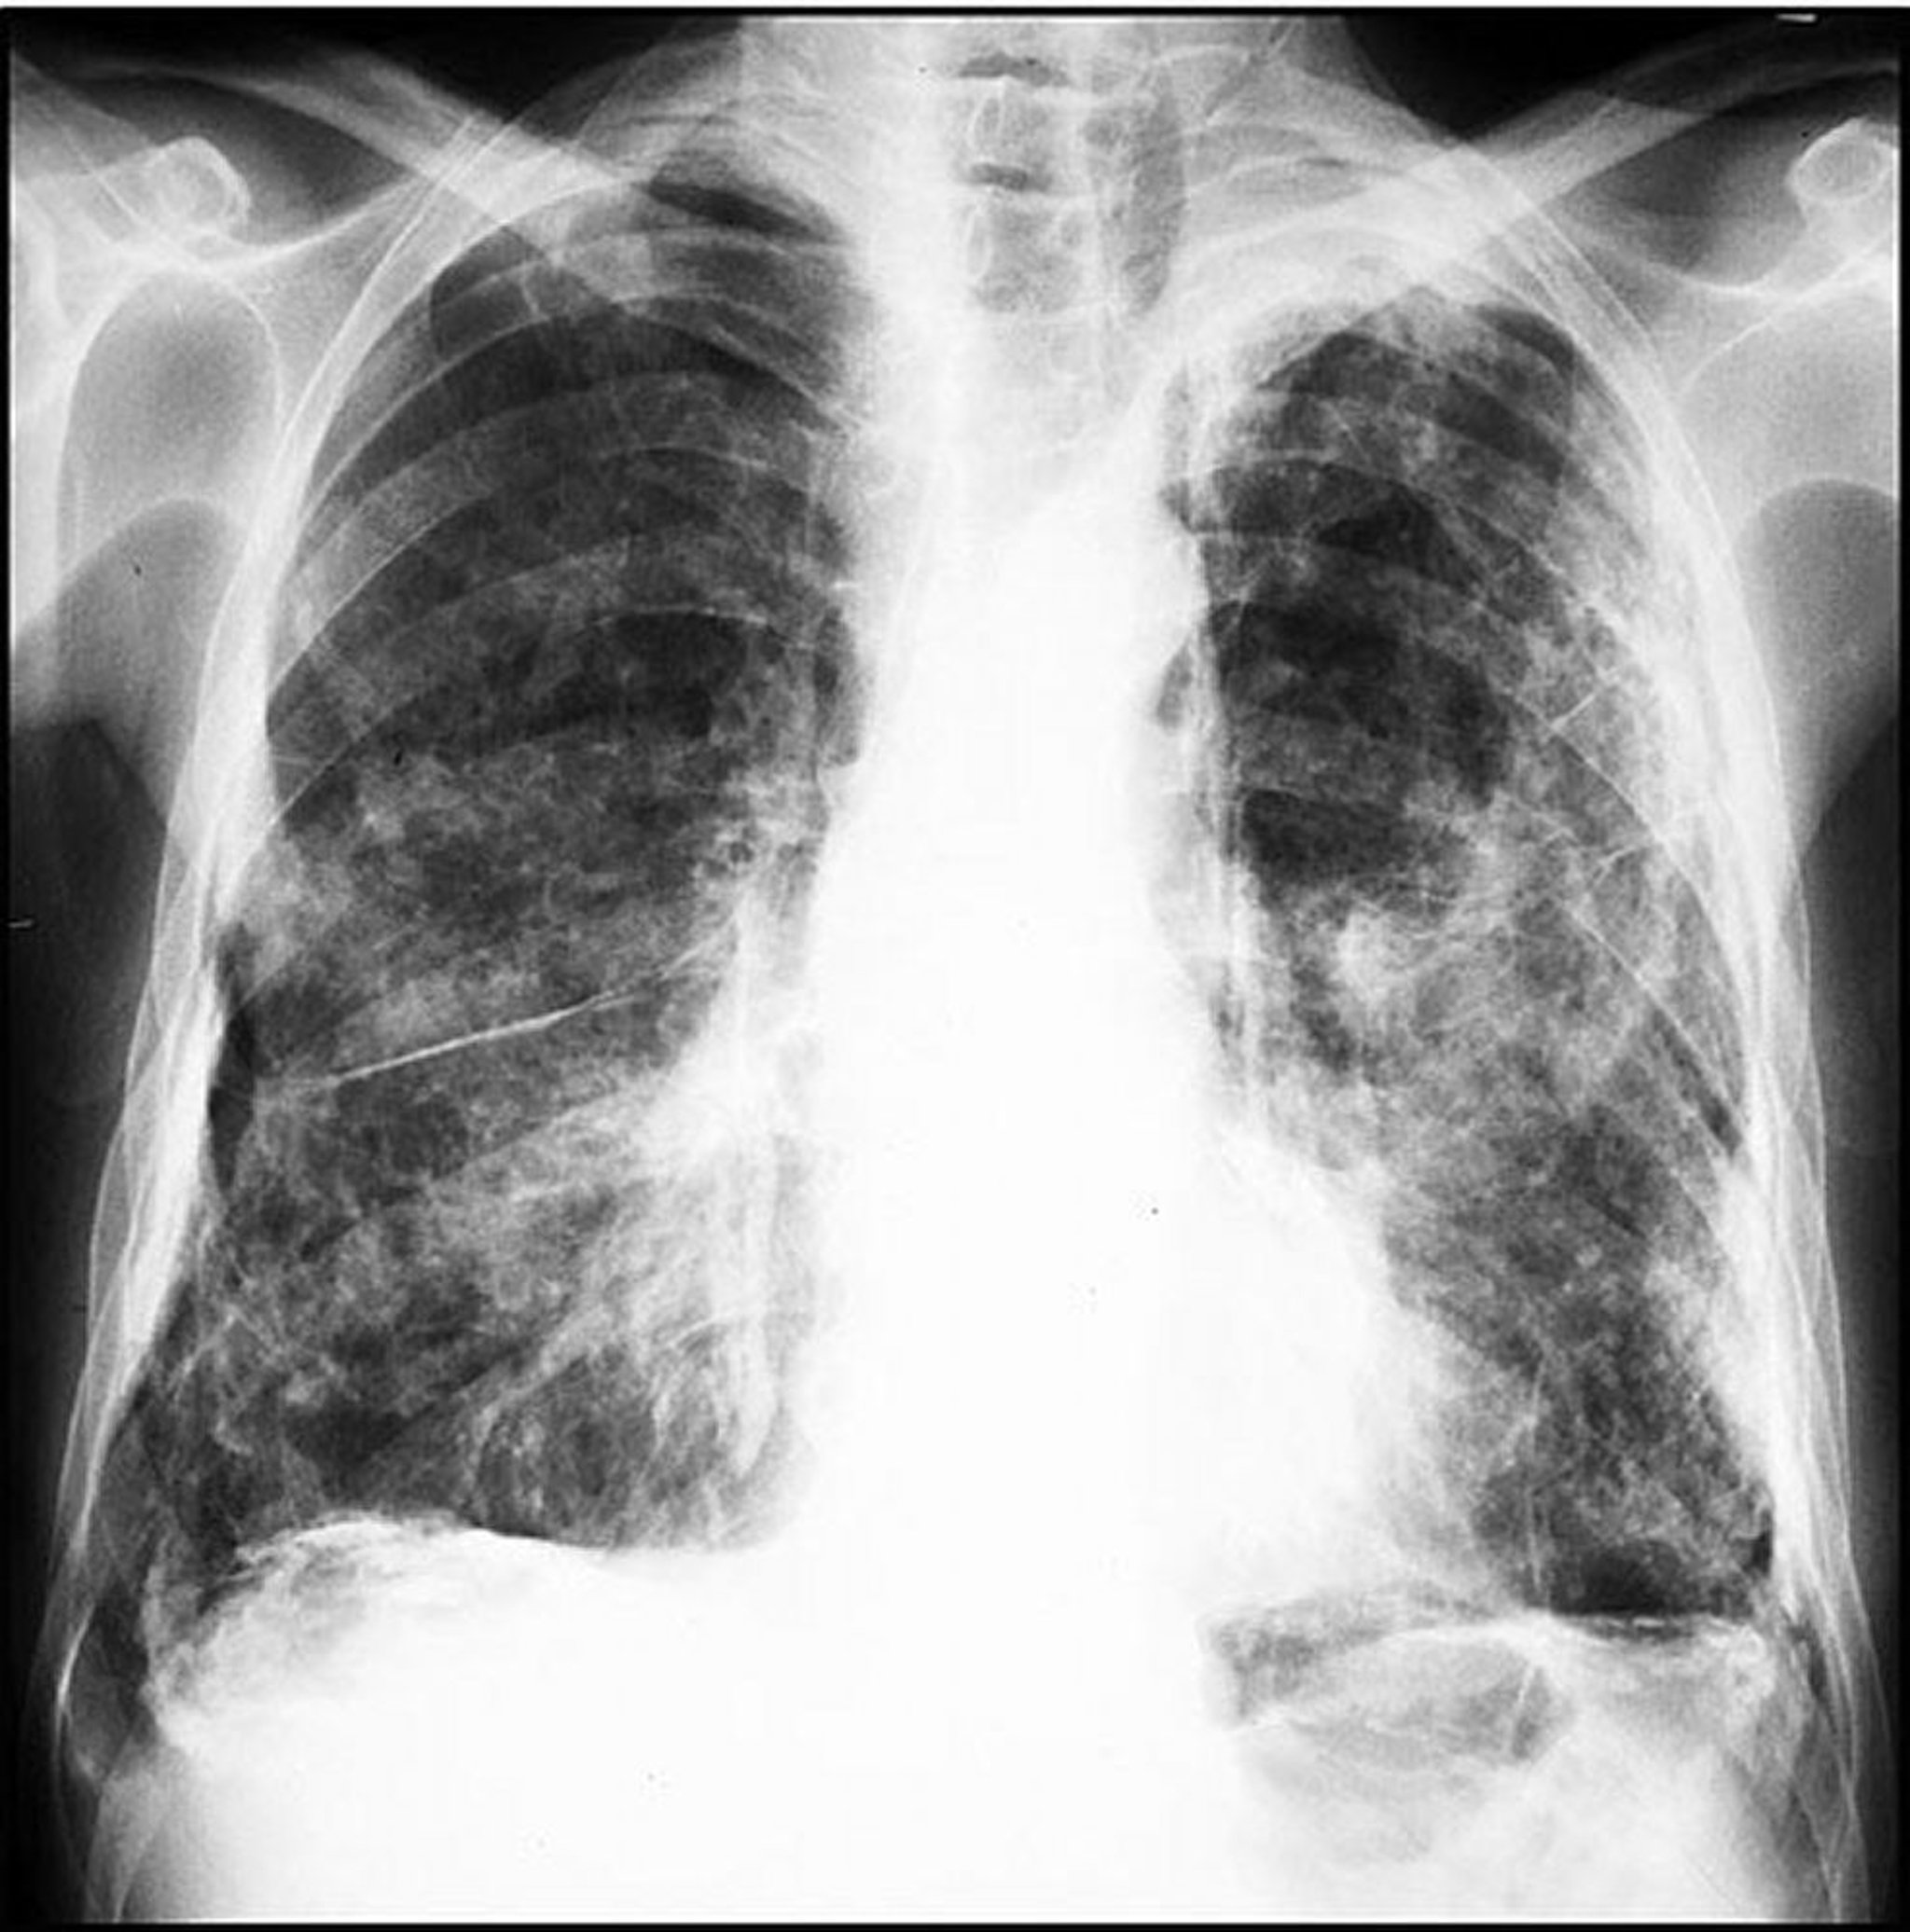

Placas relacionadas con el amianto (asbesto) extensas

Image courtesy of David W. Cugell, MD.